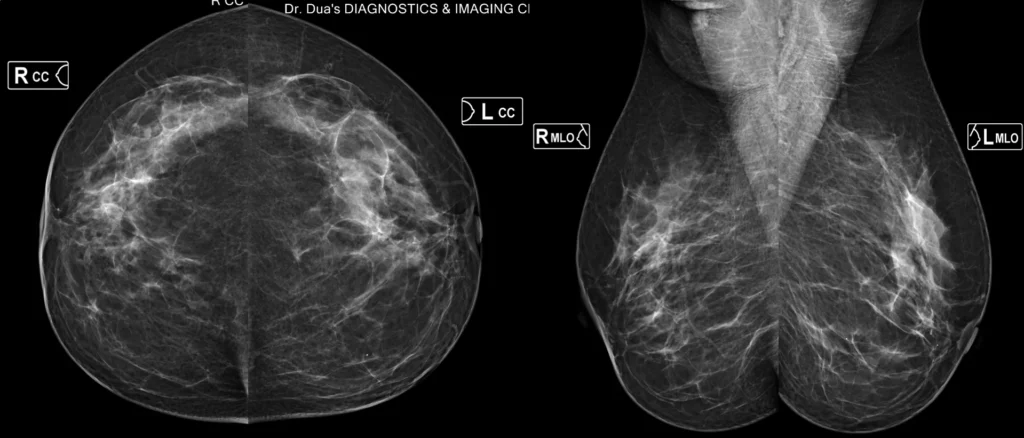

Digital Mammography

Advanced Breast Cancer Screening with Digital Mammography

Early detection saves lives. We offer world-class Mammography using low-dose, high-resolution technology interpreted by a fellowship-trained Breast Imaging Radiologist from PGI, Chandigarh.

Our system delivers high-resolution images at significantly lower radiation, ensuring safe, reliable screening.

A mammogram is a low-dose X-ray of the breasts used to detect:

• Early breast cancer

• Calcifications

• Lumps or asymmetries

• Architectural distortions

• Changes in dense breast tissue

It is the gold standard for breast cancer screening worldwide.